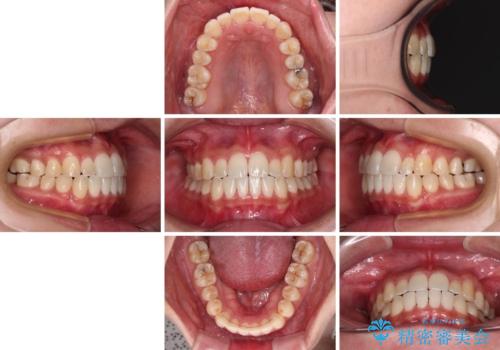

すきっ歯とオープンバイトをインビザラインで改善

- インビザライン

- 1年2ヶ月

- 前歯の上下スペースと前歯の隙間を気にして来院された患者様です。

インビザラインにより上下の前歯の隙間を閉じていくこととしました。

上下の隙間に舌が入り込むことが、すきっ歯やオープンバイトの原因であったため、舌の筋肉のトレーニングも並行して行い、後戻りの抑制を図りました。